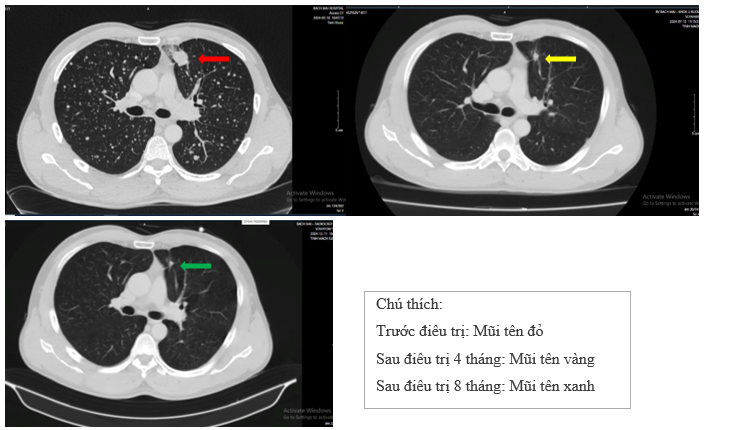

- Chụp cắt lớp vi tính lồng ngực

Hình 4: So sánh phim chụp cắt lớp vi tính lồng ngực trước điều trị với phim chụp sau điều trị 4 tháng kích thước khối u thùy trên phổi trái từ 28x24 mm giảm còn 10x8 mm, phim chụp sau điều trị 8 tháng khối u phổi trái giảm còn 9x6 mm, hạch trung thất từ 14x7 giảm còn 10x8 mm.

- Chụp cắt lớp vi tính ổ bụng

Hình 6: Phim chụp CT ổ bụng sau điều trị 8 tháng gan có kích thước bình thường, bờ đều, nhu mô đồng nhất, không thấy khối khu trú. Tuyến thượng thận 2 bên thanh mảnh. Như vậy đã không còn hình ảnh nốt bất thường tại gan, tuyến thượng thận trái tại so với phim cũ ở Hình 1